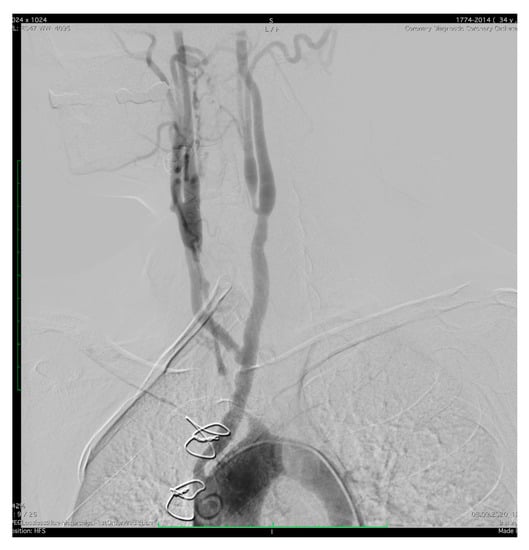

2. Case Presentation